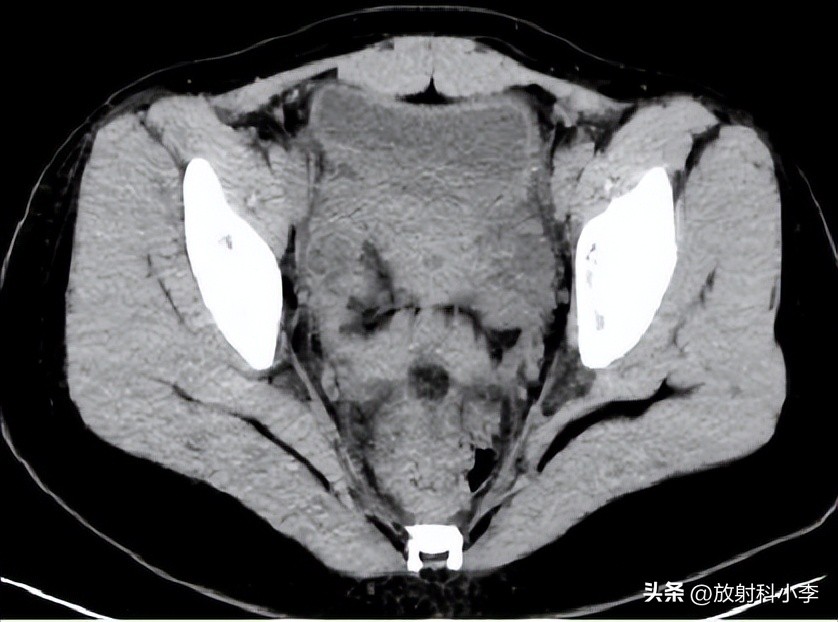

case 3.

A,B.平扫CT示子宫腔内低密度灶,双侧宫旁间包块,呈囊实性改变;C,D.增强CT示宫腔内肿块强化程度低于子宫肌层;双侧宫旁病变多囊状改变,囊壁较厚,与周围组织结构分界不清。

术后诊断:子宫内膜癌,及双侧卵巢输卵管脓肿